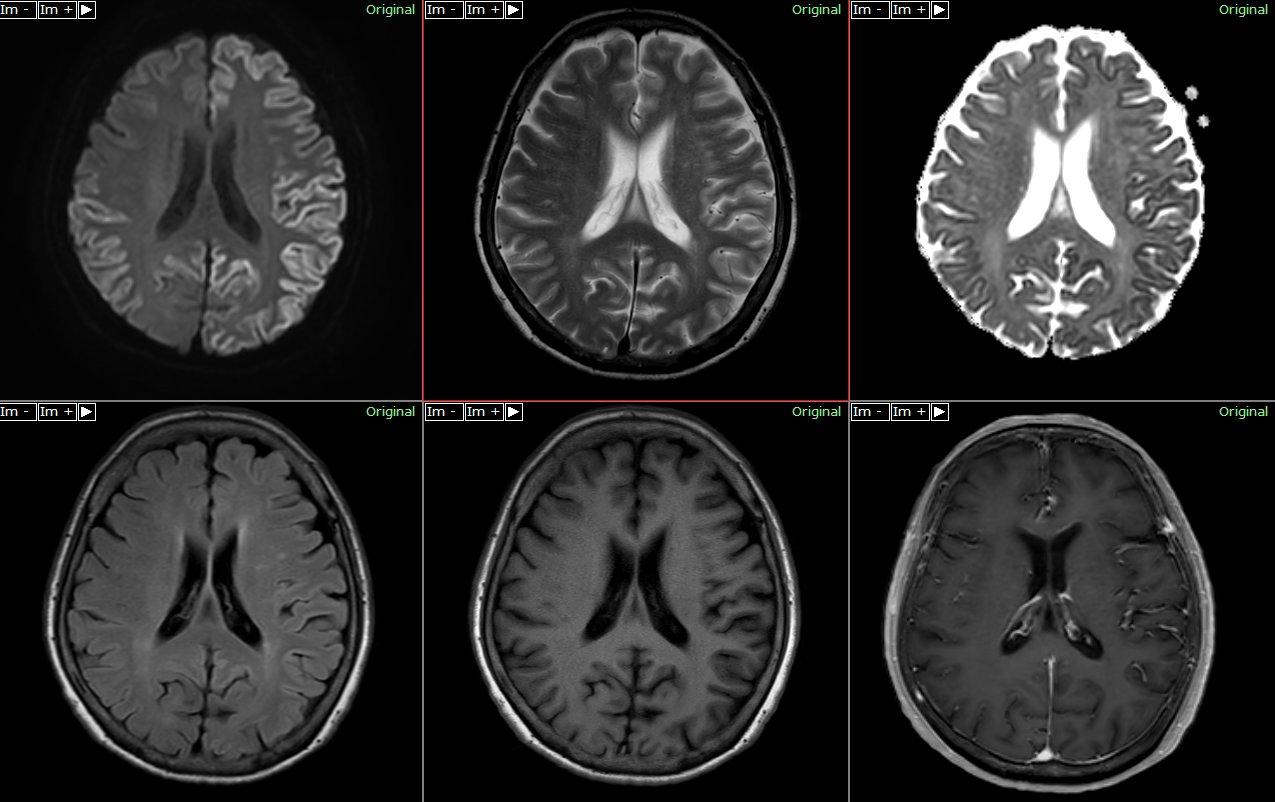

Imaging of CreutzfeldtJakob Disease Imaging Patterns and Their Creutzfeldt-Jakob Disease Stages It occurs worldwide and has several forms and subtypes. Further divided into numerous subtypes according. Creutzfeldt-Jakob Disease Stages.

Figure 2 from Imaging and EEG findings of Rare Heidenhain Variant of Creutzfeldt-Jakob Disease Stages It occurs worldwide and has several forms and subtypes. Further divided into numerous subtypes according. Creutzfeldt-Jakob Disease Stages.